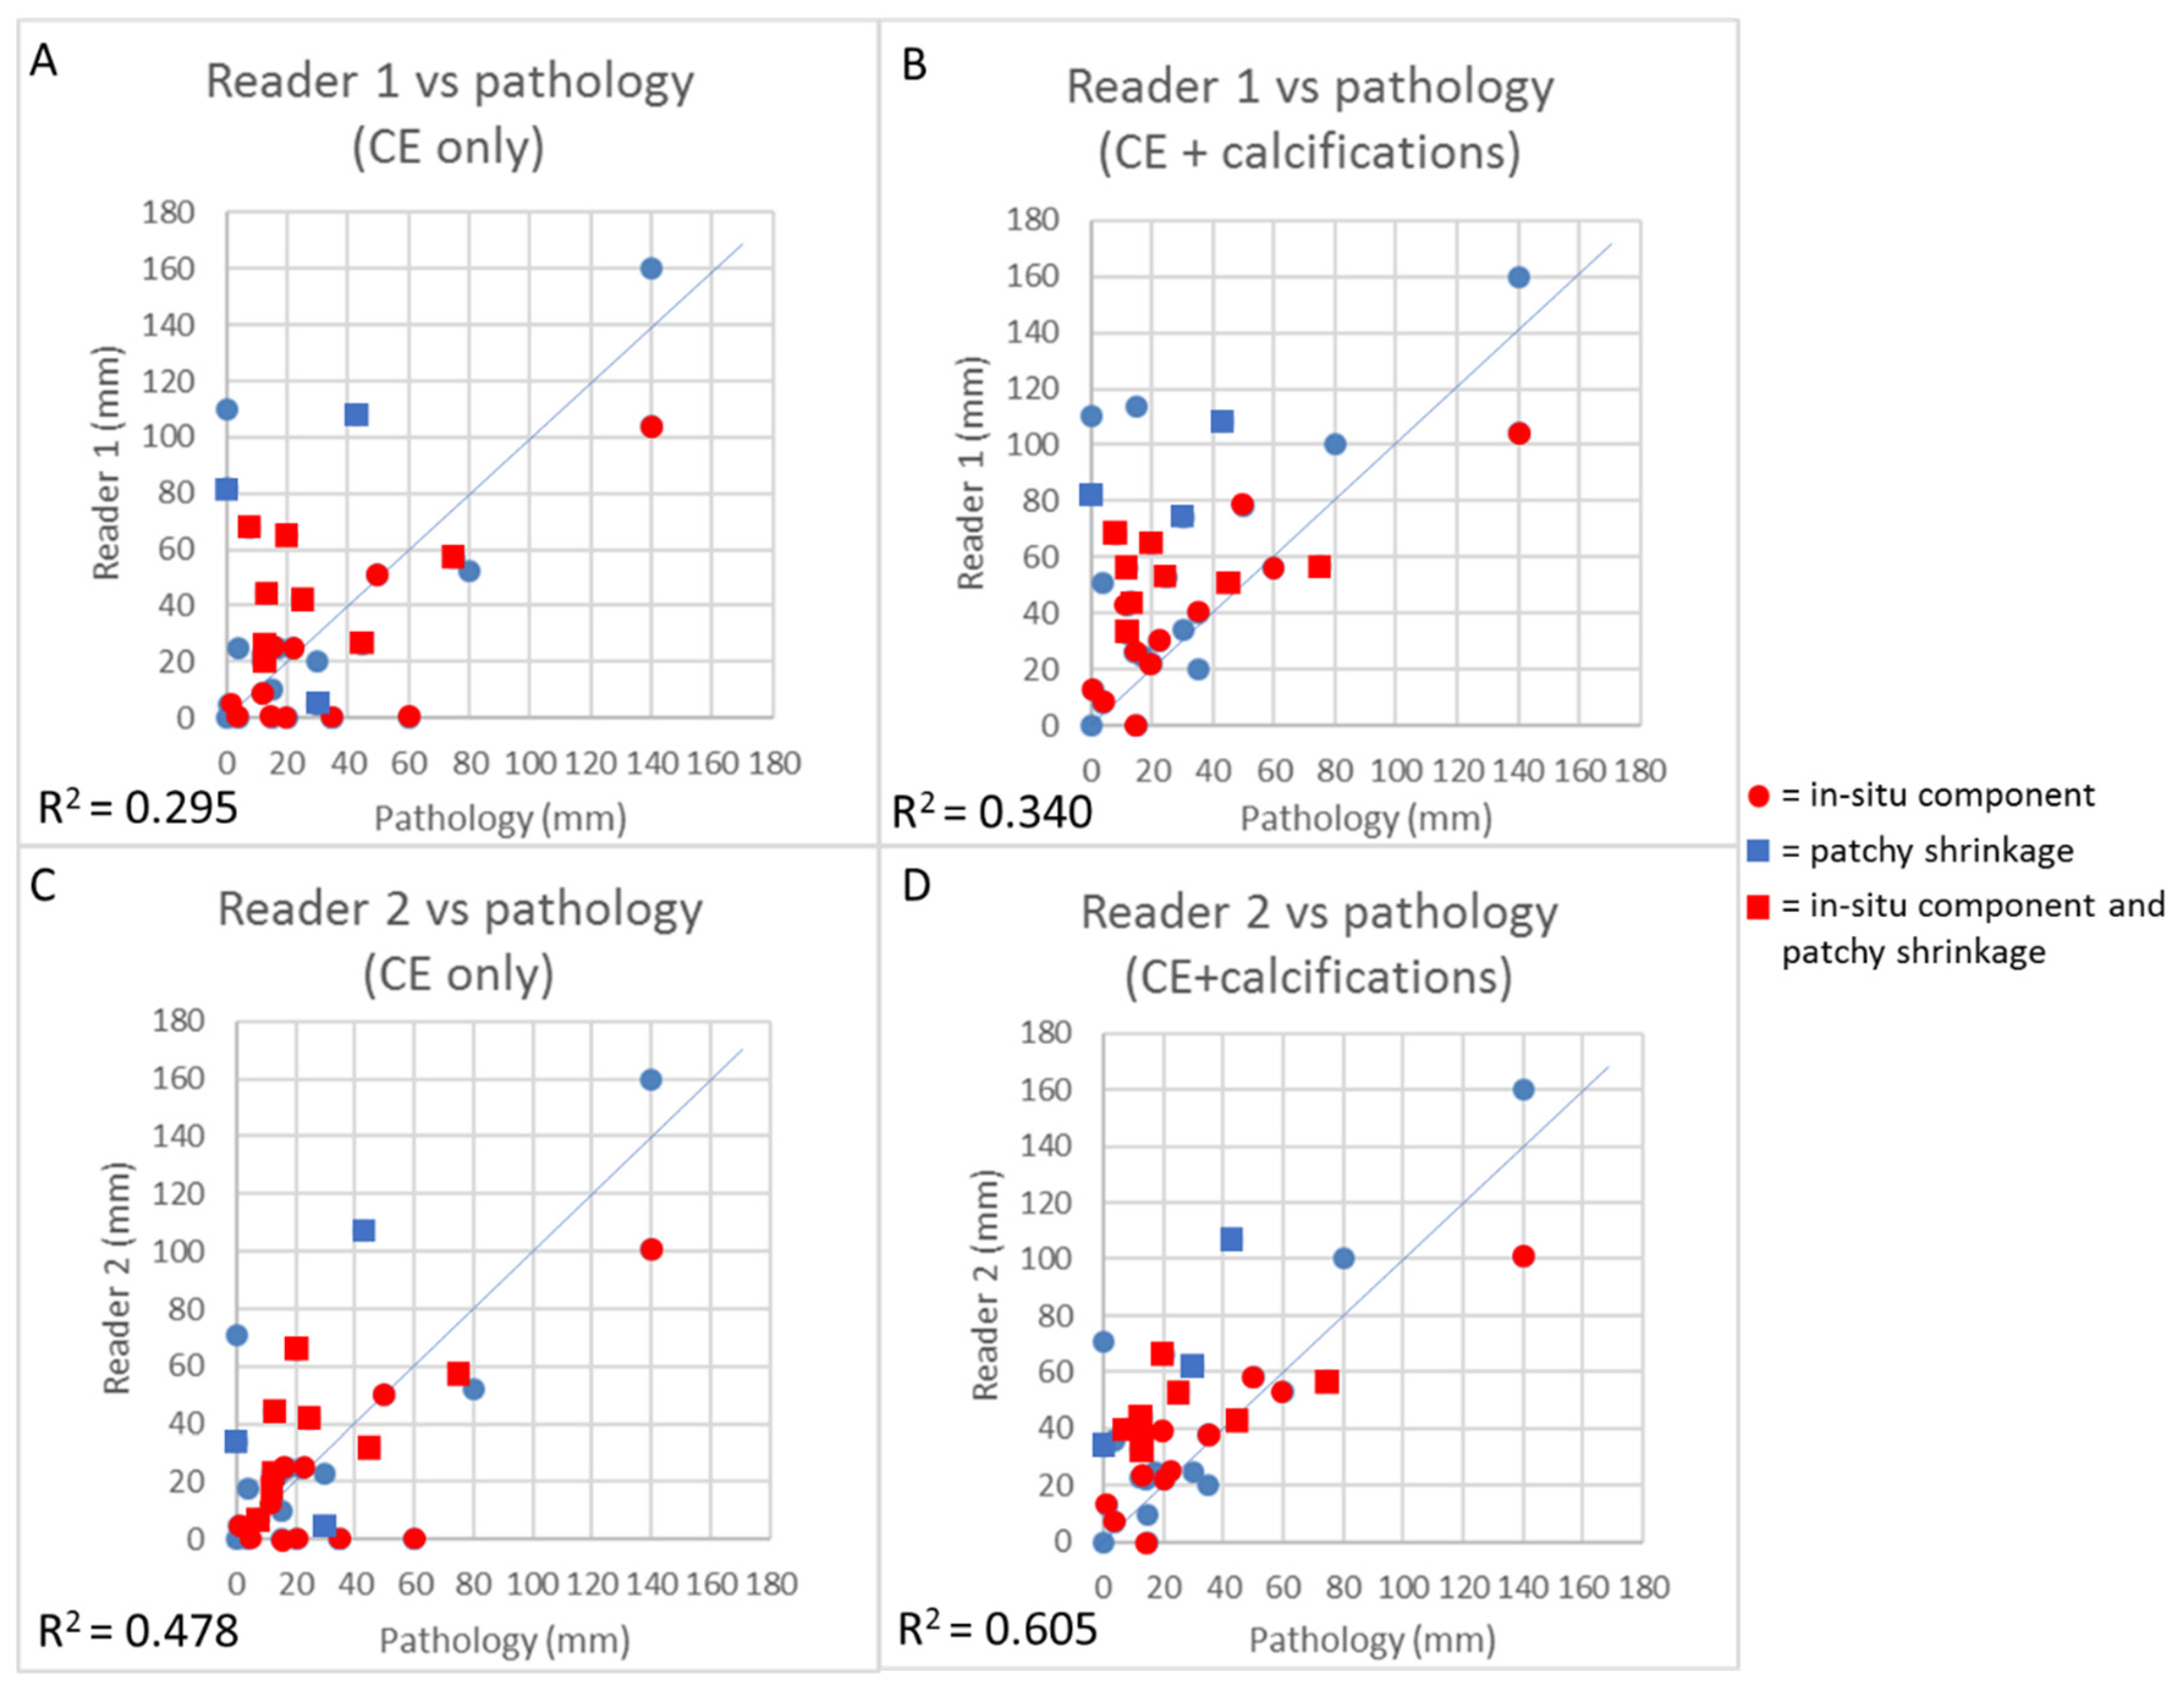

3.4. Concordance Between CEM and Pathology in the Measurement of Residual Tumor Size

3.5. CEM Reproducibility